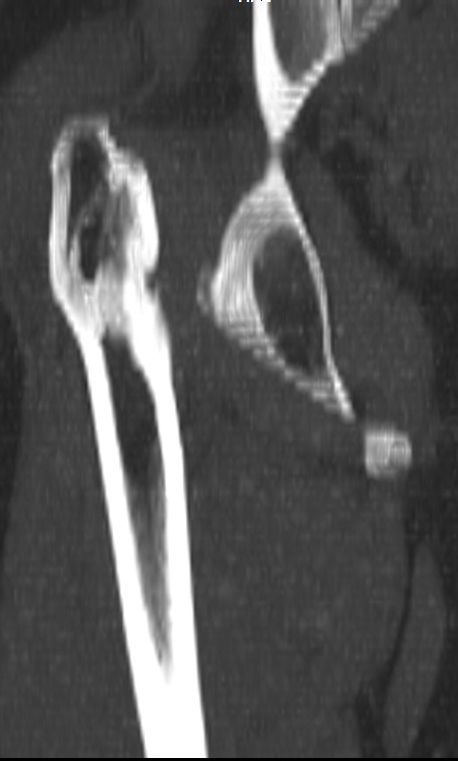

Сделал ей КТ.

С удивлением узнала, что перелом в области шейки у неё не сросся, хотя на рентгенограмме тех лет так оно и есть.

КТ - во вложении.

Интересна функциональная адаптация - практически полная функция того, что раньше было тазобедренным суставом.

>К нам обратилась пациентка 29 лет. В 9 летнем возрасте, падение с

>качелей. Перелом правого бедра: диафиза и шейки. Рентгенограмм нет, но

>судя по рассказам пациентки, перелом шейки бедра нашли через два месяца

>консервативного лечения перелома диафиза. Через 2 месяца после травмы

>оперативное лечение перелома диафиза накостным остеосинтезом, шейку

>лечили консервативно.